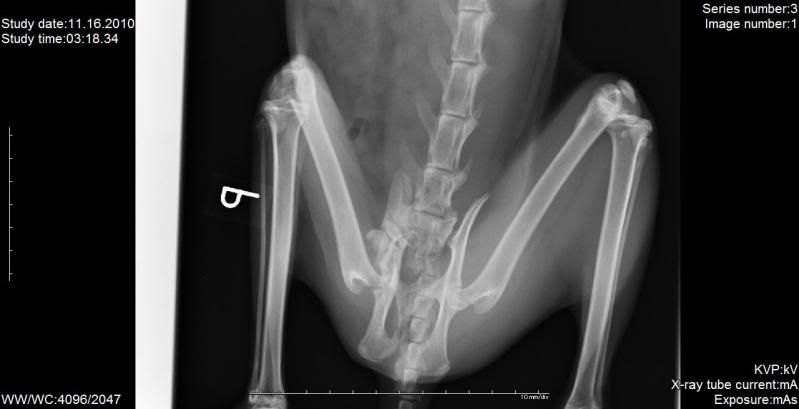

a co do Merlinka to myślę, że będzie ok bo on próbuje stawać na tej nodze, czasem się nią podpiera, ale zaraz cofa... wyraźnie widać, że boli, a jak boli znaczy że działa